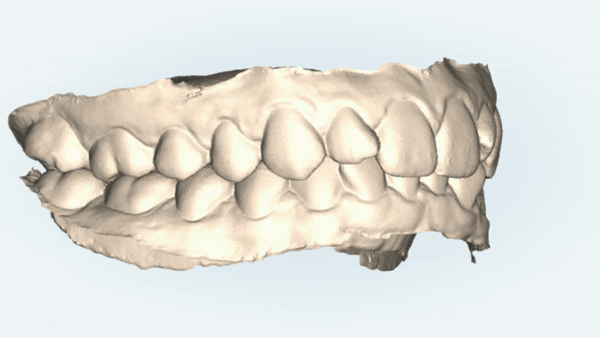

비발치 세라믹교정을 통해

솟아올라 있던 아래 앞니를 함입시켜

전반적으로 완만한 아치형태를 만들고

삐뚤빼뚤했던 치열이 고르게 교정되고

악궁또한 바른 U자 모양으로 개선되었습니다.

3D CT, i-tero 구강스캐너 등

다양한 진단 장비를 갖춘 유펜바른치과에서